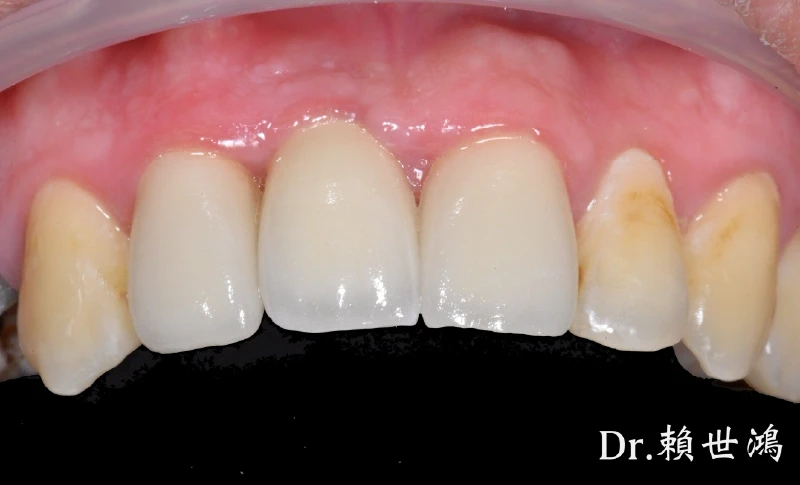

大家來猜猜看哪一個植牙、假牙、真牙?

這位患者的治療挑戰涵蓋了缺牙、受損牙齒的修復,以及對最終美觀的極高要求。我們透過一系列數位化、微創化的治療流程,成功重建了患者的口腔健康與自信笑容。

前牙區可見多顆牙齒的齒質狀況與根尖健康需要處理。根管治療成功完成,並搭配全瓷冠進行修復,重建了牙齒的形態與強度。

前牙區修復後的全瓷冠,無論在顏色、透光度還是形態設計上,均與自然牙完美融合,邊緣密合度高,牙齦健康。

揭曉答案!